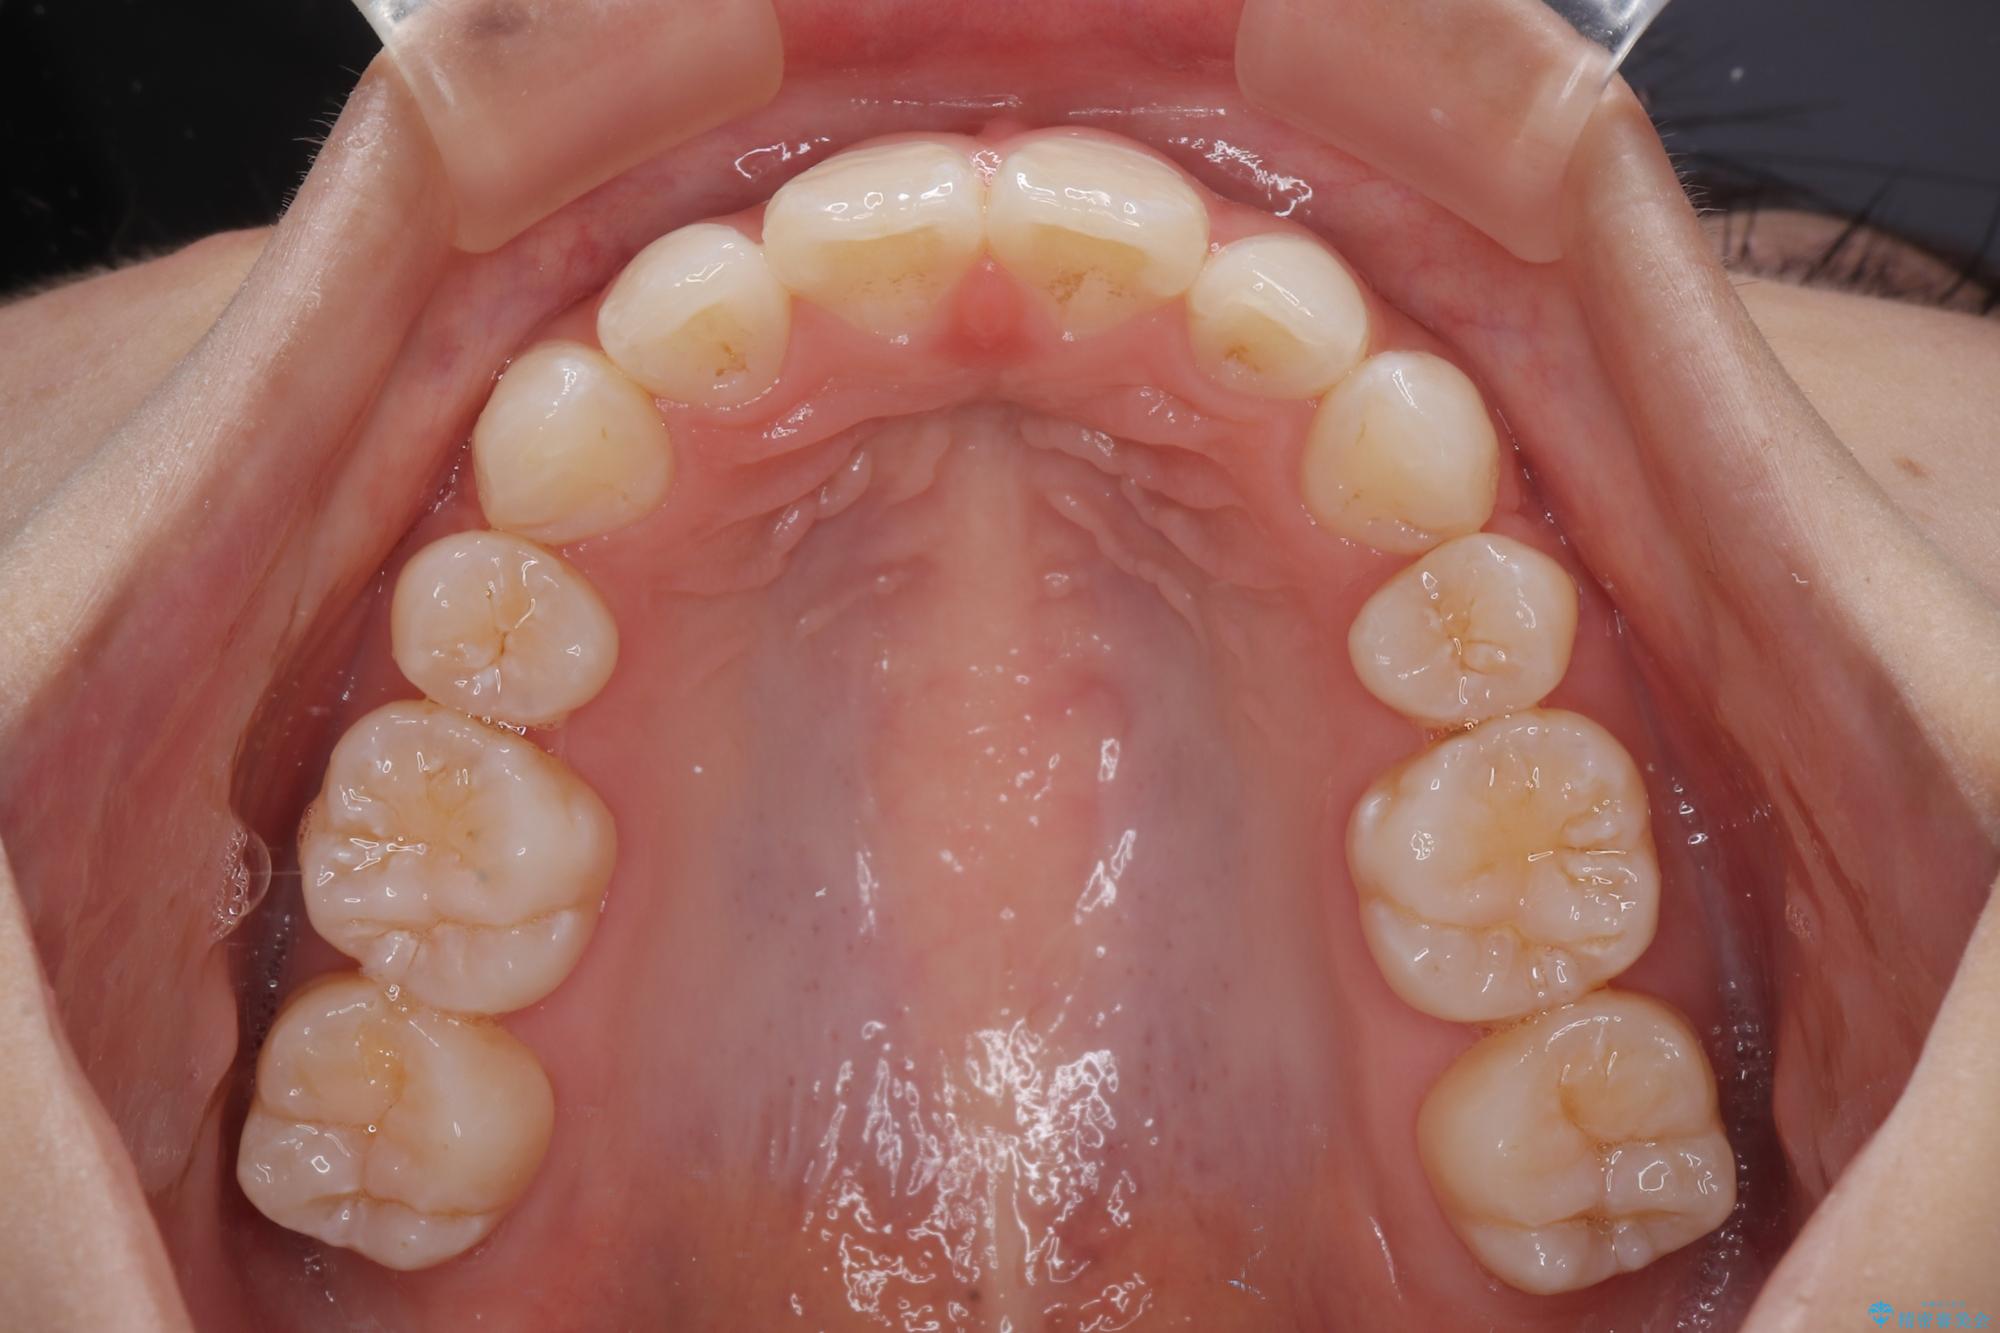

下唇に前歯が当たって跡が残ってしまう状態でしたが、スッキリとした口元に仕上げることができました。

- 口を閉じたときに飛び出してしまう上顎前歯を気にして来院された患者様です。

下顎はデコボコが気になっていたため、上下左右第一小臼歯4本を抜去して、ワイヤー装置にて口元の突出感を改善するよう矯正治療を行うこととしました。